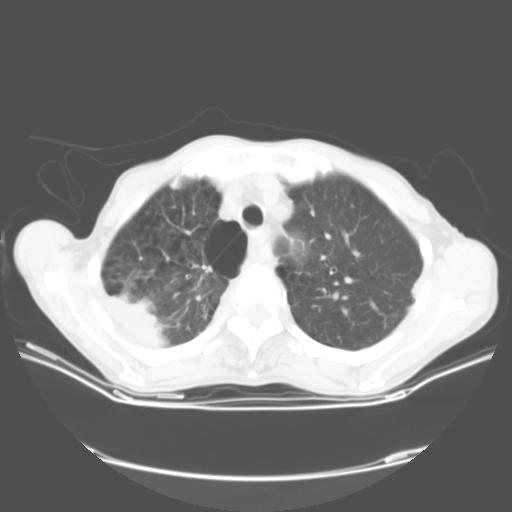

女,72岁,咳嗽一周余,突发右下肢无力二天。

来院做头颅+胸部ct平扫

胸部病变平扫35hu,增强强化至70hu

这个病人首先是胸部病变的定位到底是肺内还是肺外。仔细观察块影位于胸膜下,与胸膜间有透亮带,且近端血管未见明显推移而是引流样改变,形态分叶,说明这个病灶位于肺内胸膜下。很可能是腺癌,腺癌最易致颅内高密度转移灶。局部胸膜有侵犯。

本例颅内见多发大小不等高密度灶,有强化及水肿;另外,胸锁关节层面可能是第四胸椎及右侧肋骨起始部骨质欠连续,椎旁软组织肿胀,建议调骨窗观察。

诊断:右下肺癌伴颅内、胸椎、肋骨转移可能性最大。